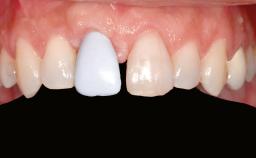

A 20-year-old woman was referred for implant therapy in 2004. Her medical history revealed no significant findings, and neither did she smoke nor take any medications. An extraoral examination revealed no abnormalities of the skin, hair or nails. The intraoral examination revealed only 11 permanent teeth clinically. These were normal in shape, size, and color. In addition, eight retained deciduous teeth (53, 62, 63, 71, 72, 73, 81, 82) were present. No abnormalities were detected during the general examination. The family history revealed that the patient’s father and two sisters were on record with similar conditions. The clinical examination revealed a thick gingival biotype. No recession of the attached gingiva was noted, but the retained deciduous teeth were mobile and unsightly. As a syndrome had not been diagnosed, the case was categorized as non-syndromic oligodontia.

Prosthesis Type FDP

SAC Level Straightforward

Defining Characteristics Up to three missing teeth to be replaced with an implant-borne restoration or restorations

Loading Protocol Conventional or early